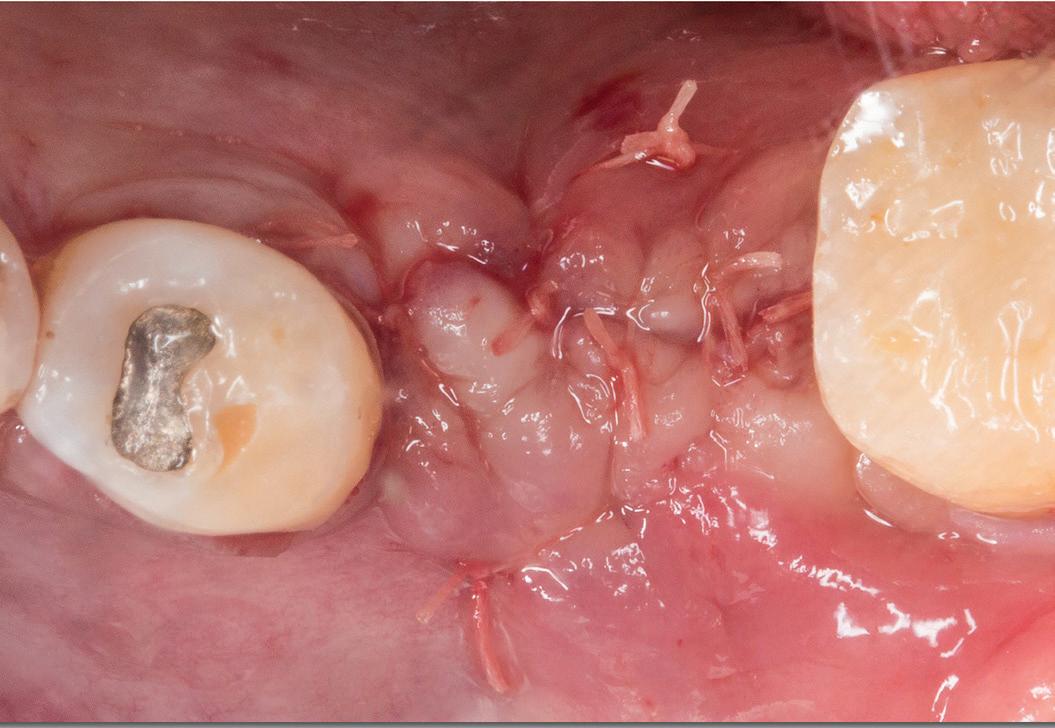

Chu44 35 M Swelling on left side of cheek FP,

Ferreira et al45 19 F Moderate headache, nausea, vomiting, left facial hypesthesia, low visual acuity FP, PP

Sohal et al46 24 M Massive swelling in right side of face FP

Linaburg et al47 50 F Massive swelling in left side of face Acanthomatous, FP

Abbreviations: F, female; FP, follicular pattern; M, male; NR, not reported; PP, plexiform pattern.

Chart. Distribution of maxillary ameloblastoma with extension into associated vital structures (N = 45).

Ameloblastomas of the jaws are commonly diagnosed in the third decade of life, and there is no sex predilection. However, ameloblastomas involving the sinuses and nasal cavities are more common in older men, as in the present case.49

Diagnosis of ameloblastoma requires clinical, radiographic, and histopathologic examinations. Clinically, sinonasal ameloblastoma can be associated with nasal obliteration, sinusitis and/or epistaxis, and less common signs and symptoms of facial swelling, headache, and tearing.42 Radiographically, primary sinonasal lesions frequently appear as radiopaque, solid lesions that fill the nasal cavity or sinus. In contrast, ameloblastoma of gnathic origin commonly presents as a unicystic or multicystic entity.42 However, this radiographic difference cannot be appreciated if the tumor involves all the vital structures and presents as a single lesion involving the maxillofacial region of that site. Histologically, ameloblastoma of jaws and sinonasal ameloblastoma have a similar appearance, commonly

Extension

Nasal cavity, orbital floor